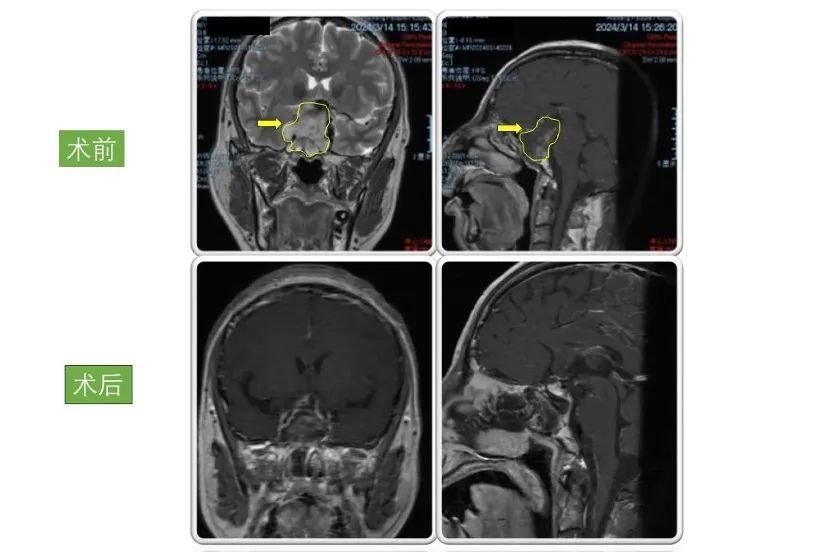

患者1

男性,46岁 因“突发头痛伴恶心呕吐、双眼视物不清12小时”入院。入院检查显示巨大垂体腺瘤,大小为4.5×4×4cm。

术后患者双眼视力明显好转,病情稳定后出院,现恢复良好,定期复查。